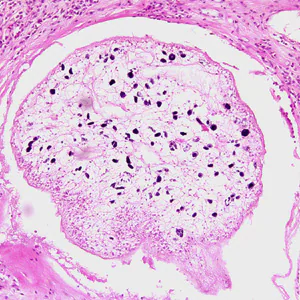

Spargana removed from tissue

Diagnosis is usually made by the recovery of a sparganum from infected tissue. The presence of a sparganum is diagnostic and identification to the species level is usually not warranted. However, the best way to identify the species is to infect an appropriate definitive host with a living sparganum and identify the adult after maturation.